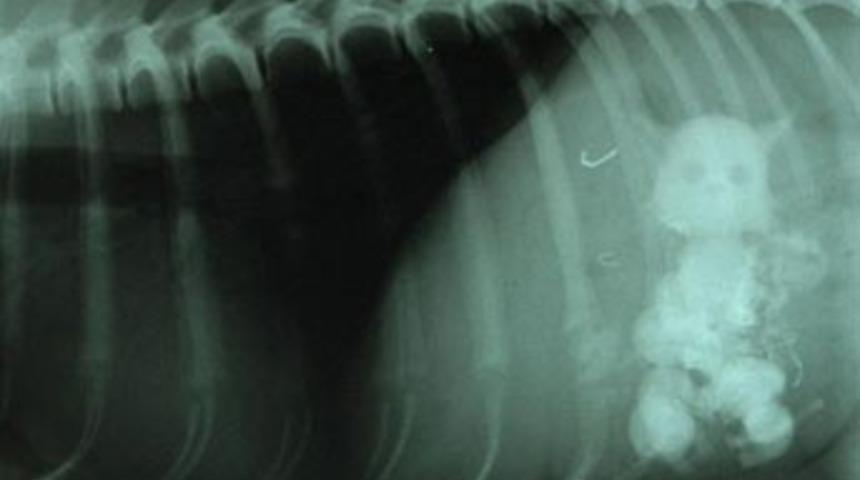

İngiltere'de terriyer cinsi köpek, beş kediyi yutunca hastanelik oldu. Sahibi tarafından hastaneye götürülen Snowy'nin röntgenlerinde evde bulunan en büyüğü 5 santimetre uzunluğundaki beş seramik kedi biblosunu yutmuş olduğu görüldü.

Köpeğin sahibi, "Röntgen sonuçları için veterinerden arayıp röntgen sonuçların 'Köpeğiniz beş kedi yutmuş' dediğinde duyduklarıma inanamadım. Gerçek kediler sandım. Neyse ki iyi olduğu için mutluyuz. Bir daha olmaması için elimizden geleni yapacağız" diye konuştu.